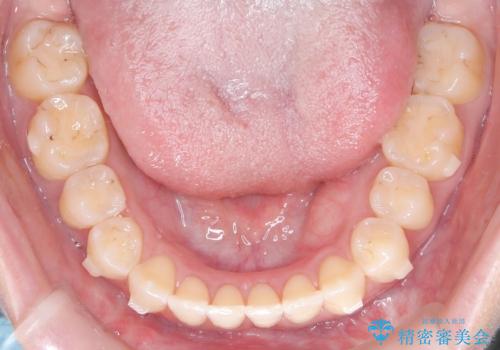

再矯正 前歯のガタツキをマウスピース矯正で治療したい

- 前に矯正治療をしたが、後戻りしてガタツキが出てきたので、治したいとのことで来院されました。

ワイヤー治療とマウスピース矯正、2通りの治療を提案させていただき、マウスピース矯正治療を希望されましたので、インビザラインによる治療を開始しました。

前歯のガタツキを改善する治療法として、マウスピース矯正が適していることが多いです。

マウスピース矯正は、金属製のブラケットやワイヤーを使用せずに、透明なマウスピースを装着して歯を移動させる方法です。そのため、目立たず、痛みも少ないです。